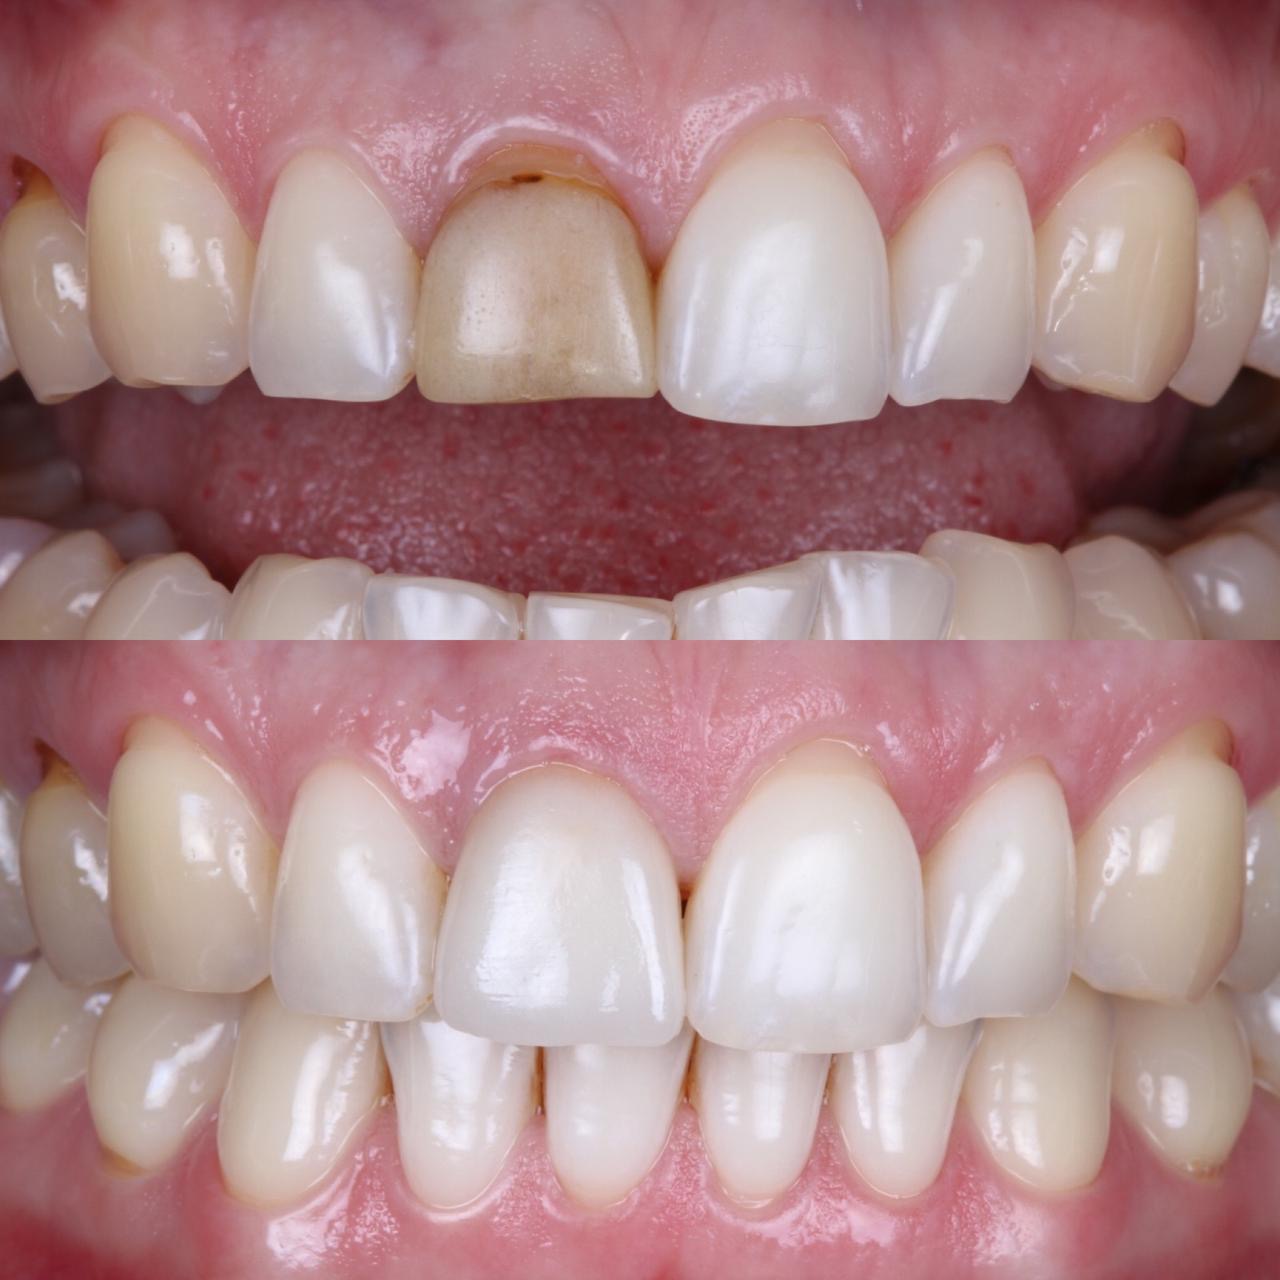

- Комплексное лечение стоматологических больных, в том числе с привлечением смежных специалистов. Функциональный анализ. Компьютерное моделирование и планированание.

- 2019г.Повышение квалификации. Курс " b.o.p.t концепция Биологически Ориентированная Техника Препарирования " под руководством Dr. Ignazio Loi

- 2008г.«Реабилитация пациентов высокоэстетичными несъемными ортопедическими конструкциями. Вкладки, накладки и виниры, изготовленные из керамики и композиционных материалов» в Стоматологическом Клиническом Учебном Центре «БиоСан»